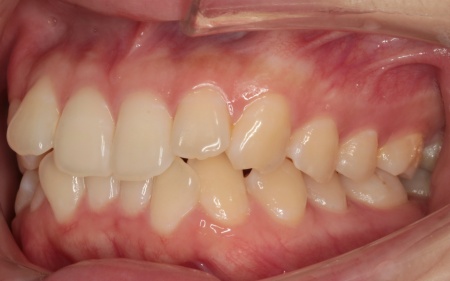

治療後

| 行った治療内容 | 患者様は「できるだけ目立たない治療方法で、なるべく早く終わらせたい」と希望されていたため、ハイブリッド矯正を提案し、同意いただきました。 ハイブリッド矯正とは、ワイヤー矯正とマウスピース矯正の両方を行う方法です。先にワイヤー矯正で歯を大きく移動させたあと、マウスピース矯正で仕上げることで、治療期間の短縮が望めます。 ただ2種類の矯正装置を使用するため、単独での矯正治療よりも費用が高くなる点がデメリットです。 ・ワイヤー矯正 歯の表面にブラケットと呼ばれるボタン状の装置を接着し、そこにワイヤーを通して歯を移動させる方法です。 患者様は目立たない治療方法を望まれていたため、ブラケットには白く目立ちにくい「セラミックブラケット」を選択しました。 ・マウスピース矯正 患者様専用のマウスピース(アライナー)を複数個作製して、定期的にご自身で交換しながら歯を移動させる方法です。 今回は、アライナーの枚数に制限がないプランである「インビザライン・コンプリヘンシブ」を選択しました。 まずは歯の表面にセラミックブラケットを装着し、ワイヤー矯正で歯を全体的に移動させます。 歯並びがある程度正しい位置に並んだら、マウスピース矯正で微調整を行いました。 歯の移動が完了したあとは定期的に経過を確認しながら、後戻りを防ぐためのリテーナー(保定装置)を継続して使用いただき、治療を終了しました。 |